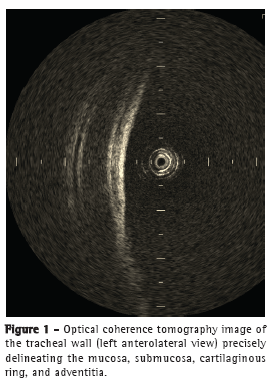

The OCT images were able to delineate, in real time, microstructures, such as the epithelium, submucosa, and cartilage, as well as the adventitia (Figure 1) of the anterior and lateral tracheal walls, similarly to the images produced by conventional histology (Figure 2). In the posterior wall, the layers corresponding to the mucosa, submucosa, and trachealis muscle were clearly differentiated on the OCT images (Figure 3) and were consistent with the histological images (Figure 4).

Imaging with OCT allowed real-time identification of microstructures, such as the epithelium, submucosa, and cartilage, as well as the adventitia of the anterior and lateral tracheal walls. In the posterior wall, it was possible to identify the mucosa, submucosa, and trachealis muscle.